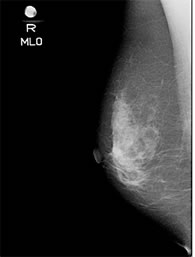

乳がん健診はマンモグラフィ検査と超音波検査があります。

| マンモグラフィ検査 | ◆早期乳がんの唯一のサインである、石灰化を写しだせる ◆過去のフィルムとの比較により、組織の微妙な変化もとらえることができる |

◆乳腺密度が低い40歳以上の方 ◆乳房が大きく、深部まで超音波が届かない場合 |